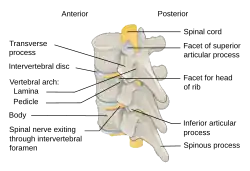

The spinal cord is housed in a bony hollow tube called the vertebral column.[3] The vertebral column is composed of many ring-like bones called vertebra (plural: vertebrae) and it spans from the skull to the sacrum. Each vertebra has a hole in the center called the vertebral foramen through which the spinal cord traverses.[3]

Laminae (singular: lamina) are the anatomical structures of primary importance in a laminotomy. Laminae are part of the vertebral arch which is the region of bone on the back side of each vertebra that forms a protective covering for the back side of the spinal cord.[3]

The vertebral arch is composed of several anatomical features in addition to laminae that must be taken into account when performing a laminotomy. In the center of the vertebral arch is a bony projection called the spinous process.[3] The spinous process is located on the posterior or back side of the vertebra and serves as the attachment point for ligaments and muscles which support and stabilize the vertebral column.[3] Each vertebra has two lateral bony projections called the transverse processes which are located on either side of the vertebral arch. Transverse processes come into contact with the ribs and serve as attachment points for muscles and ligaments that stabilize the vertebral column.[3] The lamina is the segment of bone that connects the spinous process to the transverse process. Each vertebra has two lamina, one on each side of the spinous process.[3]

During a laminotomy, the individual lies on his or her stomach with the back facing up towards the physician.[1] An initial incision is made down the middle of the back exposing the vertebrae on which the laminotomy will be performed.[1] In this procedure, the spinous process and the ligaments of the vertebral column are kept intact, but the muscles adjacent to the vertebral column known as the paraspinous muscles (example: spinalis muscle) must be separated from the spinous process and vertebral arch.[1] In a unilateral laminotomy, these muscles are detached only from the side on which the laminotomy is being performed. During a bilateral laminotomy, these muscles must be removed on both sides of the vertebrae.[1] The ligaments connecting the lamina of upper and lower vertebrae, known as Ligamenta flava are often removed or remodeled in this procedure to adjust for the small amount of bone lost.[2] Using either a microscope or an endoscope to have a visual of the procedure, a small surgical drill is used to remove a part of bone from one or both laminae of the vertebrae.[1] Laminotomies can be performed on multiple vertebrae during the same surgery; this is known as a multi-level laminotomy.[1]